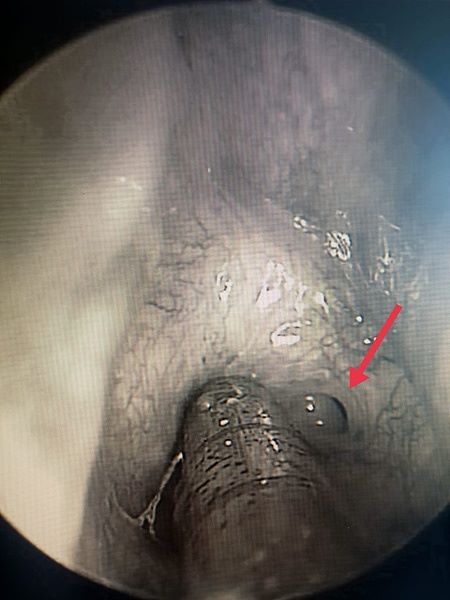

Проведена эндоскопия полости носа гибким эндоскопом: в левую половину носа эндоскоп проходит до носоглотки без препятствий, справа - большое количество слизи.

После санации правой половины носа визуализируется частичная мембранозная атрезия хоаны.